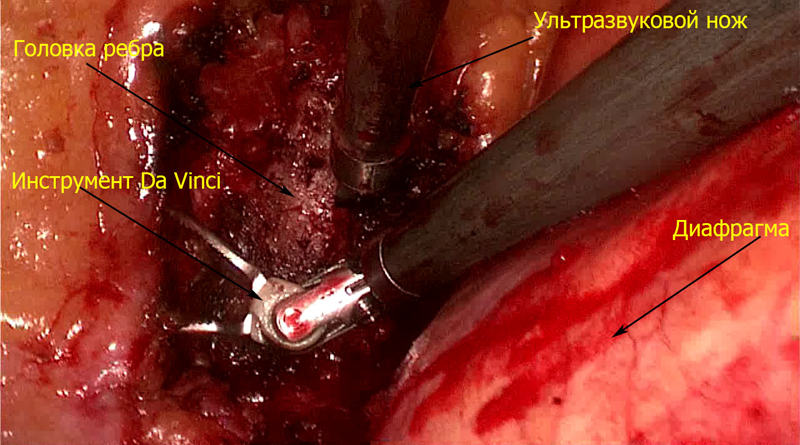

Впервые в России выполнена робот-ассистированная операция с использованием системы «Da Vinci» на грудном отделе позвоночника по поводу оссифицированной грыжи межпозвонкового диска с компрессией спинного мозга

Проведены операции с применением роботизированного хирургического комплекса «Da Vinci» при опухолях средостения — вилочковой железы